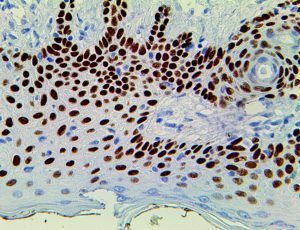

It is the ICU physician who is most likely to witness one of the deadliest manifestations of the abnormal immunological response, the cytokine storm syndrome (CSS). This response is also referred to by some as the cytokine release syndrome (CRS). CSS is characterized by continuous activation and expansion of macrophage and lymphocyte populations, which secrete large amounts of cytokines, causing the cytokine storm. This massive cytokine release is akin to hemophagocytic lymphohistiocytosis (HLH) disease, a syndrome characterized by initial unchecked and persistent activation of cytotoxic T lymphocytes and NK cells.

Clinical and laboratory manifestations of HLH include fever, enlarged liver and/or spleen, neurologic dysfunction, coagulopathy, liver dysfunction, cytopenias (i.e., low levels of erythrocytes, leukocytes, and/or platelets), hypertriglyceridemia, hyperferritinemia, hemophagocytosis, and eventually diminished NK cell activity as the immune system becomes progressively paralyzed. HLH can be familial (primary HLH) or secondary to another disease process (sHLH), such as rheumatic disease, in which it is referred to as macrophage activation syndrome (MAS, characterized by elevated ferritin).